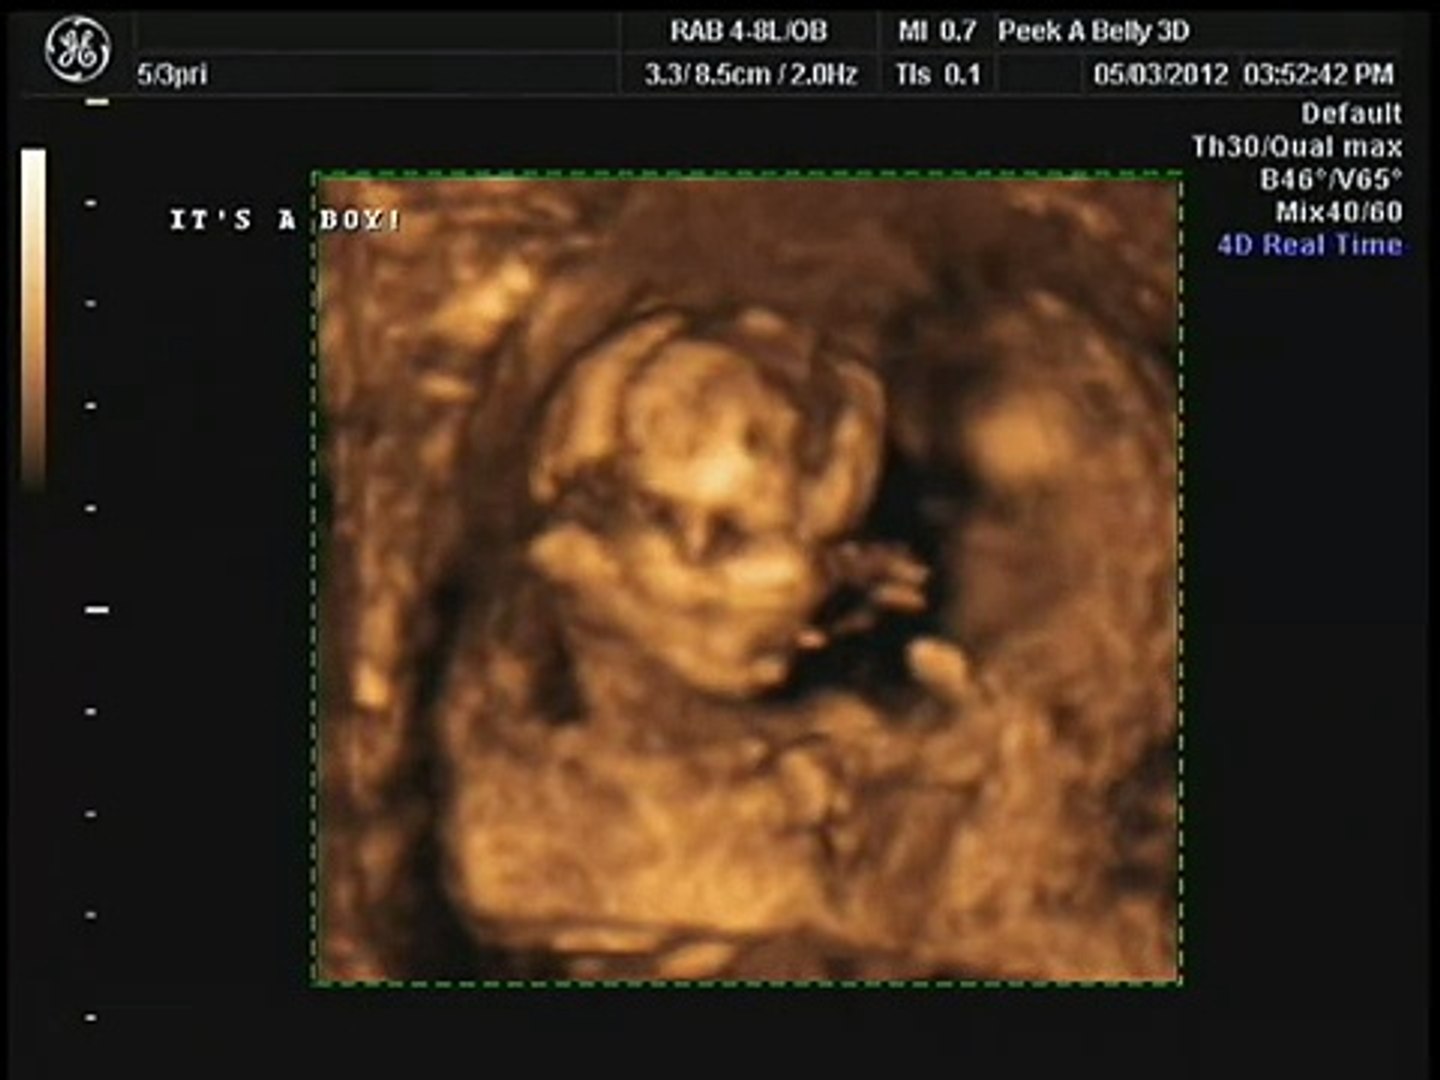

3D4D imaging is available at all stages in your pregnancy but the most popular time is between 28-32 weeks. Currently ACOG recommends that expecting women have at least one 2D ultrasound between weeks 18 to 22 of pregnancy noting that some women may also have a first-trimester ultrasound.

15 week 3d ultrasound. Mostly the fundal height at 15 weeks of pregnant is 15 cm. US says 15 weeks but at the end of the US it is recalculated to 16 GA. We did a 3D Ultrasound and at the time my wife was 15 weeks pregnant.

HD Live technology available Gender determination starting at 15 Weeks. We decided to go to one of those ultrasound places this weekend. 18 weeks 35 weeksRecommended 28-33 weeks for best face pictures 15 min 3D4D5DHD ultrasound Gender determination optional Listen to babys heartbeat 4 color printed photos Keepsake double photo folder DVD video of recorded scan.

Your doctor may notice your body changes using a tape measure. 3D 5D ultrasound images and 4D ultrasound video can be obtained at any stage. Scheduled sometime between 18 and 22 weeks of gestation the 20-week ultrasound is also often referred to as an anatomy scan.

Your 15 weeks pregnant ultrasoundwill clearly suggest that your uterus is growing with your growing baby. MEETING MY NEW SON NOAH MICHAEL VARGAS. Does it get any better than this.

They will measure fundal height which is the distance between your pubic bone and the top of the uterus. 16 Weeks pregnant full ultrasound of baby Boy. HB heartbeat was 155.

However we do recommend a gestational age of 26-34 weeks for the best facial detail. The one I had at 16 weeks with my son was correct I paid to have a 4d scan which is better detailed than a normal ultrasound. Baby Girls First UltrasoundWhen we found out it was a Girl and got to see her little hands and feet.

At this stage the baby has put on some weight and filled out to make features more visible yet still enough fluid in front of babys face to obtain great images. Sneak Peek 3D is a facility providing 3D4D Ultrasounds to expectant parents. CD of pictures to printshare Free rescan if.

I was for sure certain we were having a girl we already have a 21 month old boy and ohh how I was wrong. 3d ultrasound at 15 weeks. 3D 4D Ultrasound Heighten your experience with 3D4D imaging.

15 week 3D4D Gender ultrasound. The golden months. Gender Determination Gender determination can be done starting at 15 weeks.

This ultrasound uses high frequency sound waves that. By this week many of those bothersome early pregnancy symptoms have disappeared and at 15 weeks youre not too big to get around or get out of your chair.